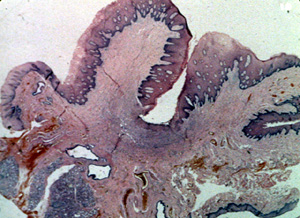

Esta microfotografía de baja resolución  ilustra bien el aspecto lobulado de la lesión. Hay una invaginación profunda en la porción central en que la pestaña de la dentadura postiza fue localizada.

Este microfotografía se observa el área ulcerada en la base de la invaginación y muestra exudado inflamatorio, tejido fibroso reactivo  y tejido de granulación.

Periférico a la ulceración el tejido del tipo predominante que comprende la mayoría de la lesión, es el tejido conjuntivo fibroso bastante denso con un número moderado de los vasos sanguíneos. Note la inflamación crónica perivascular  tan común en las lesiones reactivas. Los fibroblastos son uniformes a lo largo  hay  considerable colágeno denso. Con esta microfotografía usted puede determinar que la única forma de eliminar la lesión es con la biopsia por escisión.